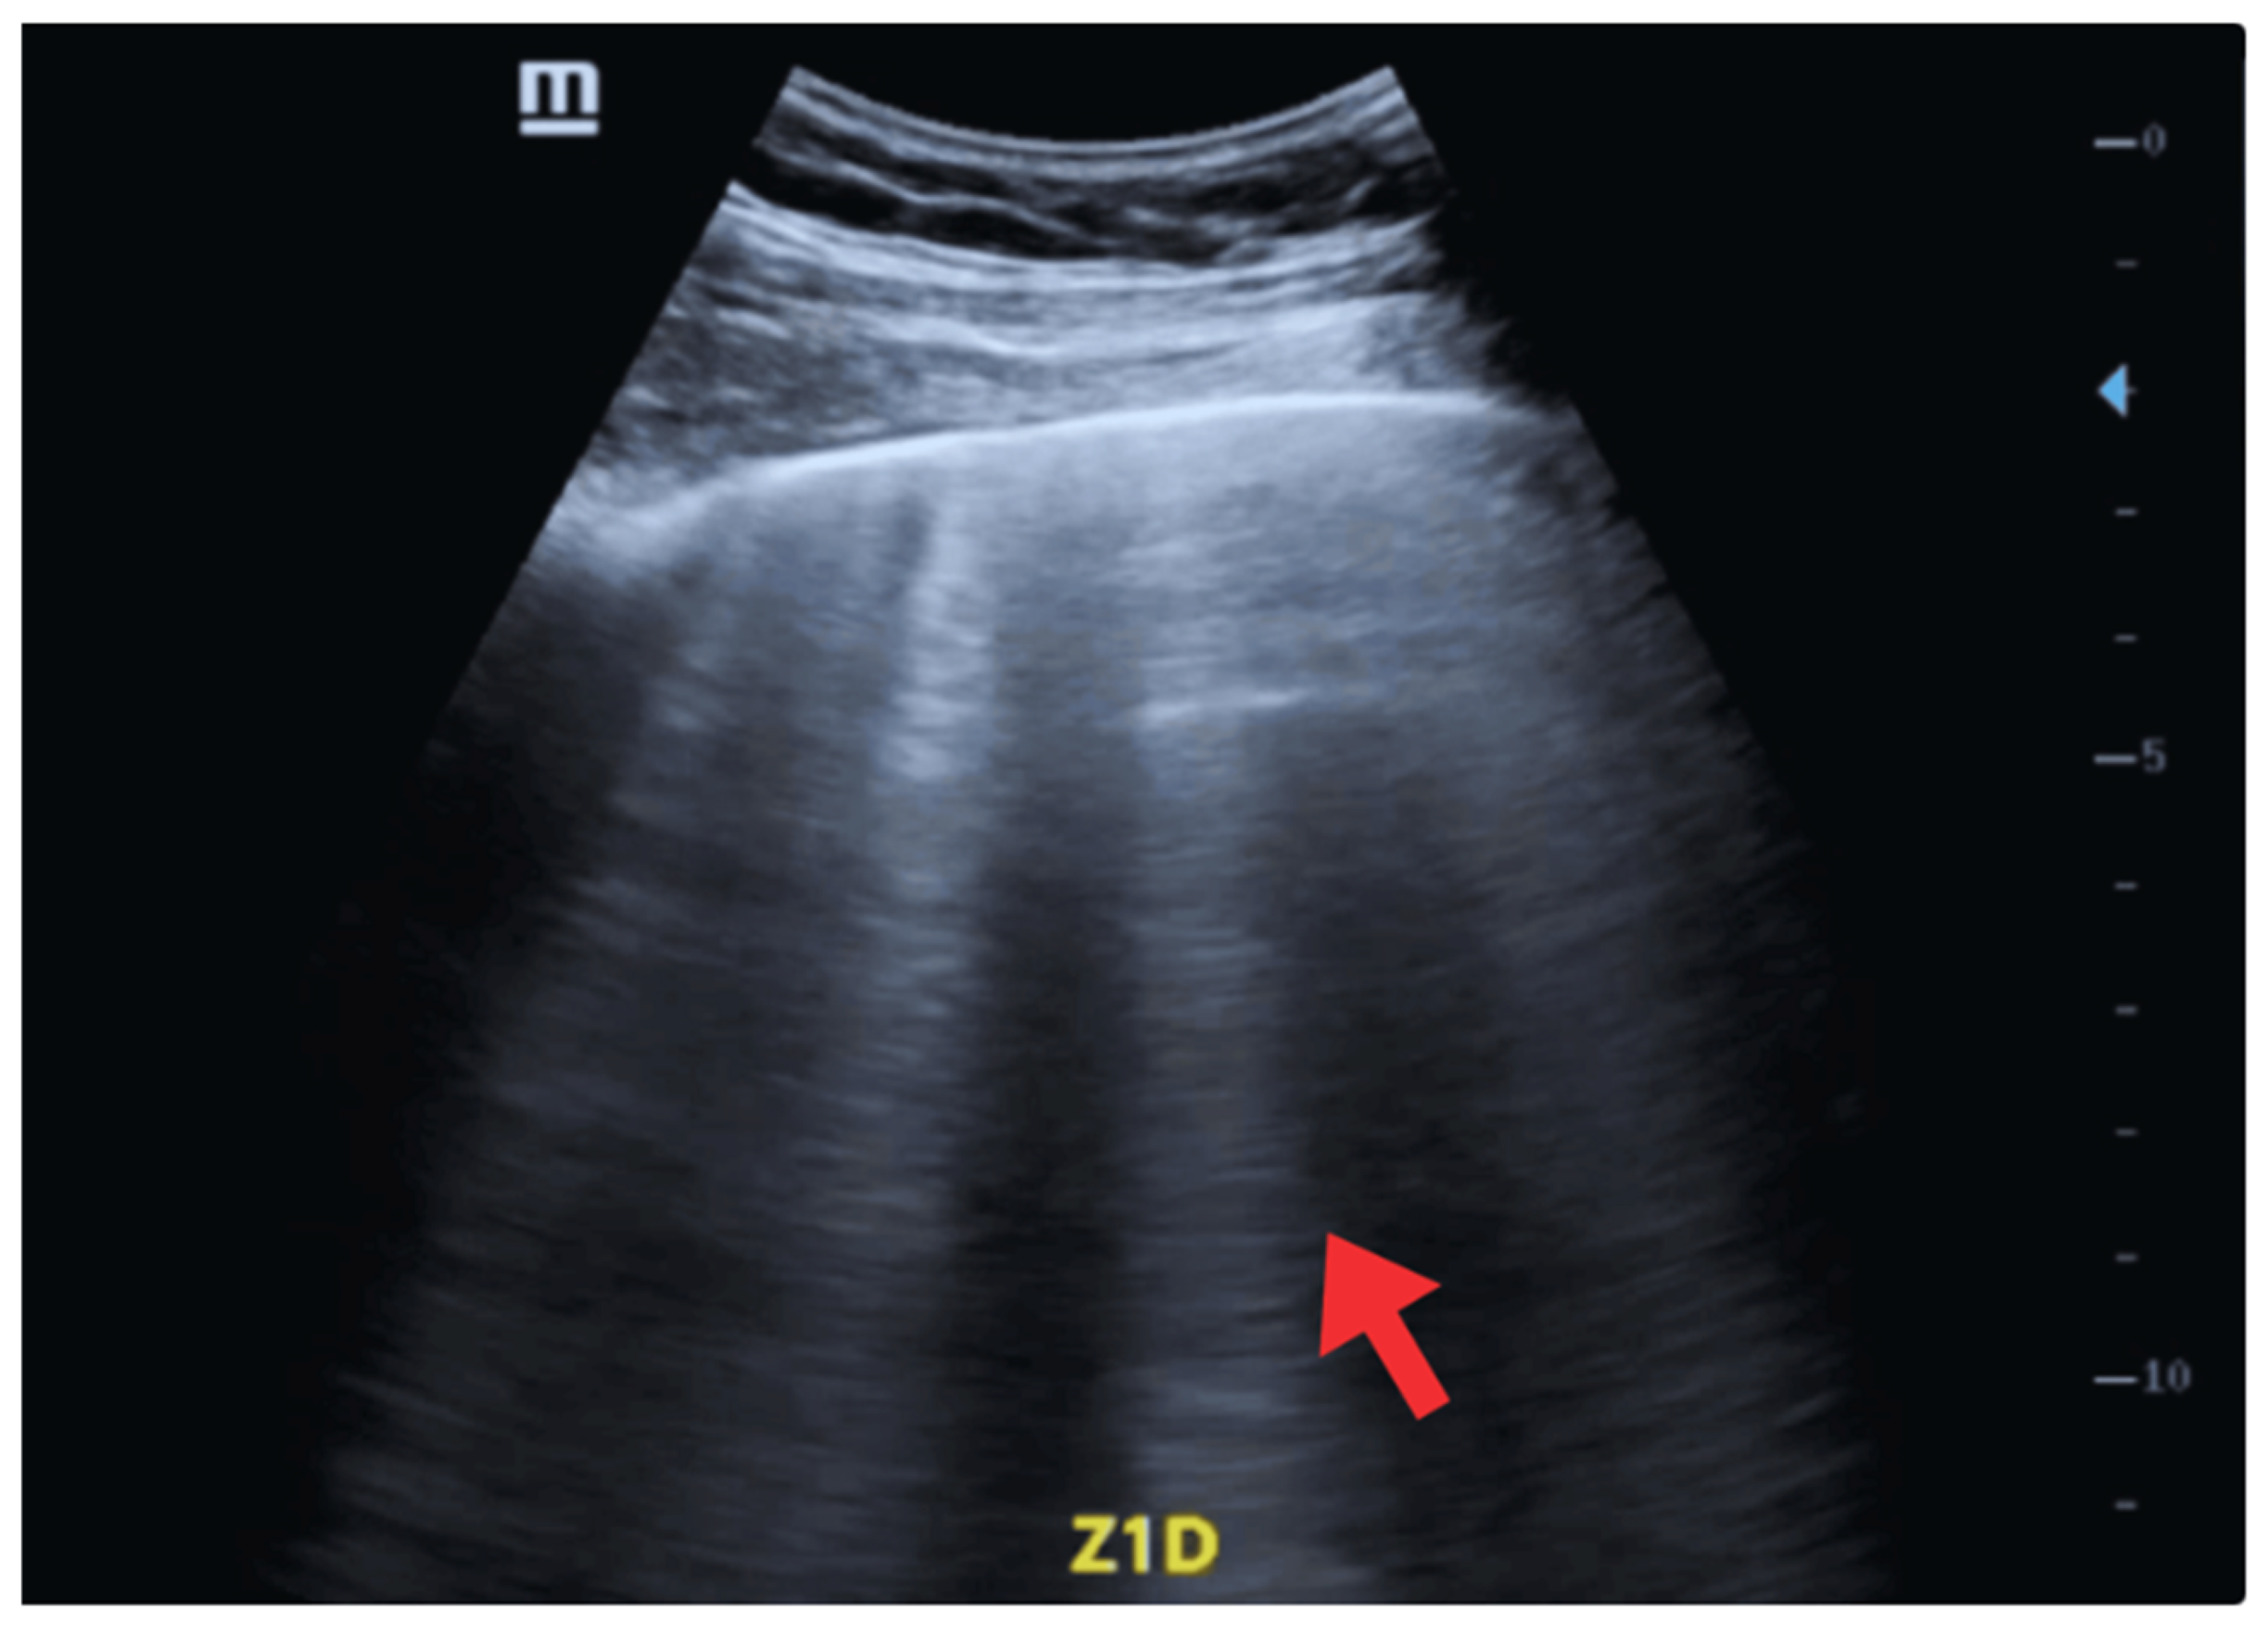

| 9–11 May | Hospital stay in an intermediate care unit. | ECG: -Rhythm: sinus (positive P wave in L1, L2, and aVF; each P wave is followed by a QRS complex). -Heart rate: 80 beats per minute. -Electrical axis: between (−60° left axis deviation). -P wave: duration ≤ 120 ms, amplitude ≤ 2.5 mm in limb leads. PR interval: 160 ms. -QRS complex: duration ≤ 110 ms. -ST segment: isoelectric. -T wave: positive in most leads, except aVR and V1. -Corrected QT interval (QTc): 400 ms. -Findings of left ventricular hypertrophy. | POCUS: -Absence of pulmonary and cardiac congestion. -Regular pleura, without thickening. -Marked reduction in B lines (<20%) in affected lung fields. -Reappearance of predominant A lines. -Absence of consolidation. Findings compatible with resolution of cardiogenic alveolar-interstitial syndrome after depleting therapy. -Ejection fraction (Simpson): 50–55% -EPSS: 7 mm (previously 10 mm). -Shortening fraction: 25%. -Less evident lateral hypokinesia. -Left chambers with reduced diameter and indexed end-diastolic volume (≤70 mL/m2). -Mild, stable, non-progressive pericardial effusion. | - |